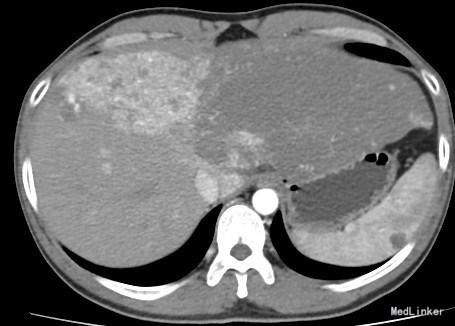

患者男,41岁,主因“发现肝血管瘤十年,上腹胀半月。”以“1.肝血管瘤 2.过敏性紫癜 ”收入院。 患者2005年体检发现肝脏多发血管瘤,最大病灶位于左叶约4.5*1.5*2.5cm,到外院就诊,建议继续观察病灶变化,患者自服中药保守治疗。之后,患者每年规律复查,2010年复查发现肝血管直径增大至10cm,患者自觉无异常不适,未及时就医治疗。半月前患者因与人冲突,上腹部受拳击后,感上腹部胀,遂到当地医院就诊。2015-11-25在外院行肝CT增强提示:肝脏内多发血管瘤,最大病灶位于左叶10.5*25.4cm,脾稍大。目前患者为求进一步手术治疗,遂来我院就诊